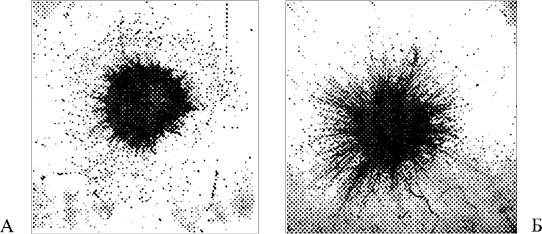

![]() Рис. 31. Эксплантаты спинальных ганглиев на третьи сутки культивирования: А – контроль; Б – в среде, в которую было добавлено 200 нг/мл вод-ного экстракта головной части лиофилизированной медицинской пиявки (об. 3,5 х, ок. 10 х) Следует отметить, что в культуру добавлялся не секрет слюнных желез пиявки, а водная вытяжка ее головного отдела, которая содержит достаточное количество веществ, экстрагируемых не только из слюнных желез, но и из нервной, мышечной, эпителиальной и других тканей, а следовательно, полученный результат может вообще не иметь никакого отношения к гирудотерапии, где в ткани попадает только секрет слюнных желез. Второй вопрос, на который эта работа не дает ответа: «Что же на самом деле растет?» Недостаток выбранной авторами модели в том, что ганглий содержит не только нервные, но шванновские и соединительнотканные клетки. Возможно, что наблюдаемый эффект связан с воздействием именно на них, а не на нейроны (например – происходит выработка волокон коллагена активированными фибробластами). Тем не менее, сама идея возможного наличия у компонентов секрета слюны медицинской пиявки прямого «трофического» действия на нервную клетку представляется нам крайне важной. Надо отметить, что эти работы были продолжены И. П. Басковой и Н. И. Чалисовой; на той же модели ганглиев куриного эмбриона. В среду добавлялась дестабилаза – компонент секрета слюнных желез. Был зафиксирован практически такой же эффект увеличения площади эксплантатов, что в какой-то степени сняло сомнения в источнике веществ, влияющих на рост ганглия. Однако по-прежнему неясен вопрос: «За счет каких клеток осуществляется рост?» Наши данные (неопубликованный материал) показывают, что дестабилаза в определенных концентрациях стимулирует выработку фибробластами волокон коллагена и эластина. Этот эффект лежит в основе регенераторного действия гирудотерапии, а в вышеописанном эксперименте мог стать причиной увеличения площади ганглия. В любом случае важность этих работ велика, и мы надеемся, что в дальнейшем появятся исследования действия секрета или компонентов слюны медицинской пиявки на нервную клетку. Пока же говорить о доказанной стимуляции роста нейритов при воздействии на них секрета слюнных желез пиявки нельзя. Вместе с тем такие эффекты гирудотерапии, как восстановление кровообращения (в том числе на микроциркуляторном уровне), уменьшение воспаления и гипоксии безусловно способствуют улучшению трофики нервных клеток. Зоны приставки пиявок такие. ![]() Зона 1. Точки черепа. Здесь в зависимости от локализации процесса могут быть рекомендованы следующие области для приставки пиявок: • височная область (3, 5, 8); • заушная область и область сосцевидных отростков (10, 11); • межбровье (1); • область основания затылочной кости (13); • точки волосистой части головы (2, 4, 6, 7); • точки кпереди от трагуса под скуловой дугой (9) и в области угла нижней челюсти (12). Зона 2. Область печени – в проекции печени и в правом подреберье (П1, 2, 3, 4, 5, 6, 7), точка на вершине мечевидного отростка (ЭГ2) и точка в проекции левой доли печени (ЭГ3). Зона 3. Воротниковая область – точка ниже остистого отростка VII шейного позвонка (СП1) и точки несколько ниже и кнаружи от нее (СП10, 11), а также точки в местах напряжения и болезненности мышц надплечья (СП14, 15). Зона 4. Область крестца – точки копчика (КР2, 3), точки проекции крестца (КР6, 7, 8, 9, 10, 11, 12, 13). ![]() Рис. 32. Зоны приставки пиявок при нарушении мозгового кровообращения Особенности проведения процедур: основной вопрос, который требует решения в ближайшие годы, – методические особенности применения гирудотерапии при ишемическом и геморрагическом инсультах. Если целесообразность применения пиявок при ишемическом инсульте не вызывает сомнений и более или менее ясны методические подходы к лечению, то возможность и методика использования пиявок при геморрагическом инсульте совсем не столь очевидны. На первый взгляд при геморрагическом инсульте пиявки противопоказаны, так как они «снижают свертываемость крови», но на самом деле это далеко не так однозначно. Прежде всего следует напомнить, что геморрагический инсульт развивается совсем не в результате понижения свертываемости крови, а снижение венозного полнокровия, противоотечное действие, уменьшение ишемии мозга и гипотензивное действие медицинских пиявок здесь имеют большое практическое значение. Следует учитывать, что, активируя постпиявочное кровотечение (с которым из организма вымывается большая часть вводимых пиявкой веществ), а также сокращая длительность приставки (неполное кровоизвлечение), мы можем существенно снизить антигемостатическое действие гирудотерапии. В любом случае при проведении гирудотерапии в связи с острым геморрагическим инсультом необходимо знать и учитывать время свертывания крови. Возможно, при таком инсульте в первые 2–3 дня не следует ставить пиявки на точки головы и шеи, но вполне оправдана их постановка на печень или копчик. Вместе с тем особенностью геморрагических инсультов является дополнительное «токсическое действие» излившейся крови на окружающие клетки мозга, что является одной из причин его менее благоприятного течения. Нам представляется, что рассасывающее и регенераторное действие гирудотерапии именно при этой тяжелой форме нарушения мозгового кровообращения может сыграть существенную положительную роль. В первые дни пиявок следует ставить ежедневно. Как правило, при ишемическом инсульте используются точки на голове. На 3-ю процедуру, когда мы ожидаем проявления приставочной реакции, пиявки следует поставить на область печени, а далее – вновь в область головы. Область копчика, а тем более крестца не стоит брать у тяжелых больных, поскольку (даже при хорошем уходе) здесь очень велика вероятность образования пролежней. Зона 4 обычно используется в более легких случаях, а также при реабилитации тяжелых больных. Важным вопросом является перспективность применения гирудотерапии у больных, перенесших инсульт достаточно давно. Если не учитывать показания, связанные с наличием гипертонической болезни и атеросклероза, а остановиться на вероятности улучшения мозговой симптоматики после гирудотерапии, то следует ориентироваться на наличие венозной гипертензии и явлений отечности тканей мозга. Они нередко достаточно ярко выражены даже спустя длительное время после перенесенного инсульта. Помимо ряда жалоб на определенный характер болевого синдрома, такие нарушения могут выявляться при осмотре глазного дна, исследовании сосудов бульбоконъюнктивы, а также по косвенным признакам – на МРТ и рентгенологическом снимке черепа. Если вы находите отечный синдром, гирудотерапия абсолютно обоснована и даст четкий клинический результат. В таких случаях с интервалом в 2 месяца следует провести 3 курса гирудотерапии примерно по 8–10 процедур. |